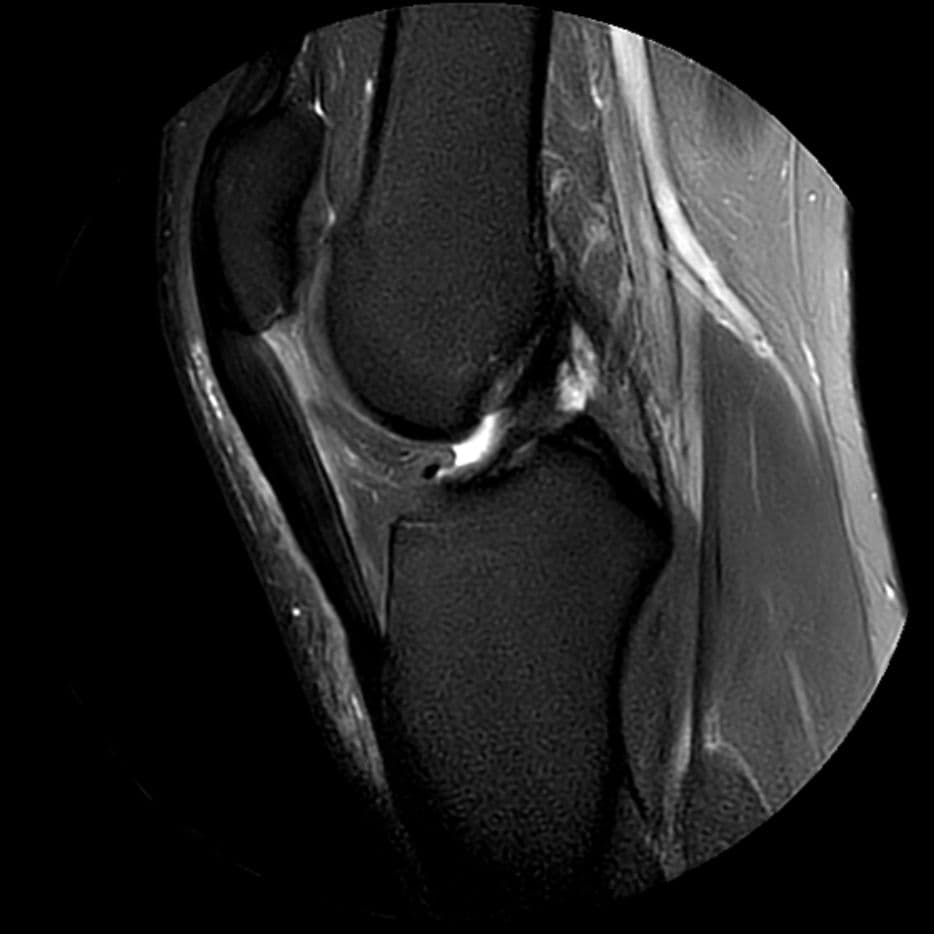

Aspect peu creusé de la trochlée.

Nette enthésopathie proximale du tendon patellaire, épaissi, œdématié, sans composante fissuraire.

Infiltration œdémateuse des parties molles circonférentielle au tendon.

Aspect IRM d'une enthésopathie proximale du tendon patellaire.